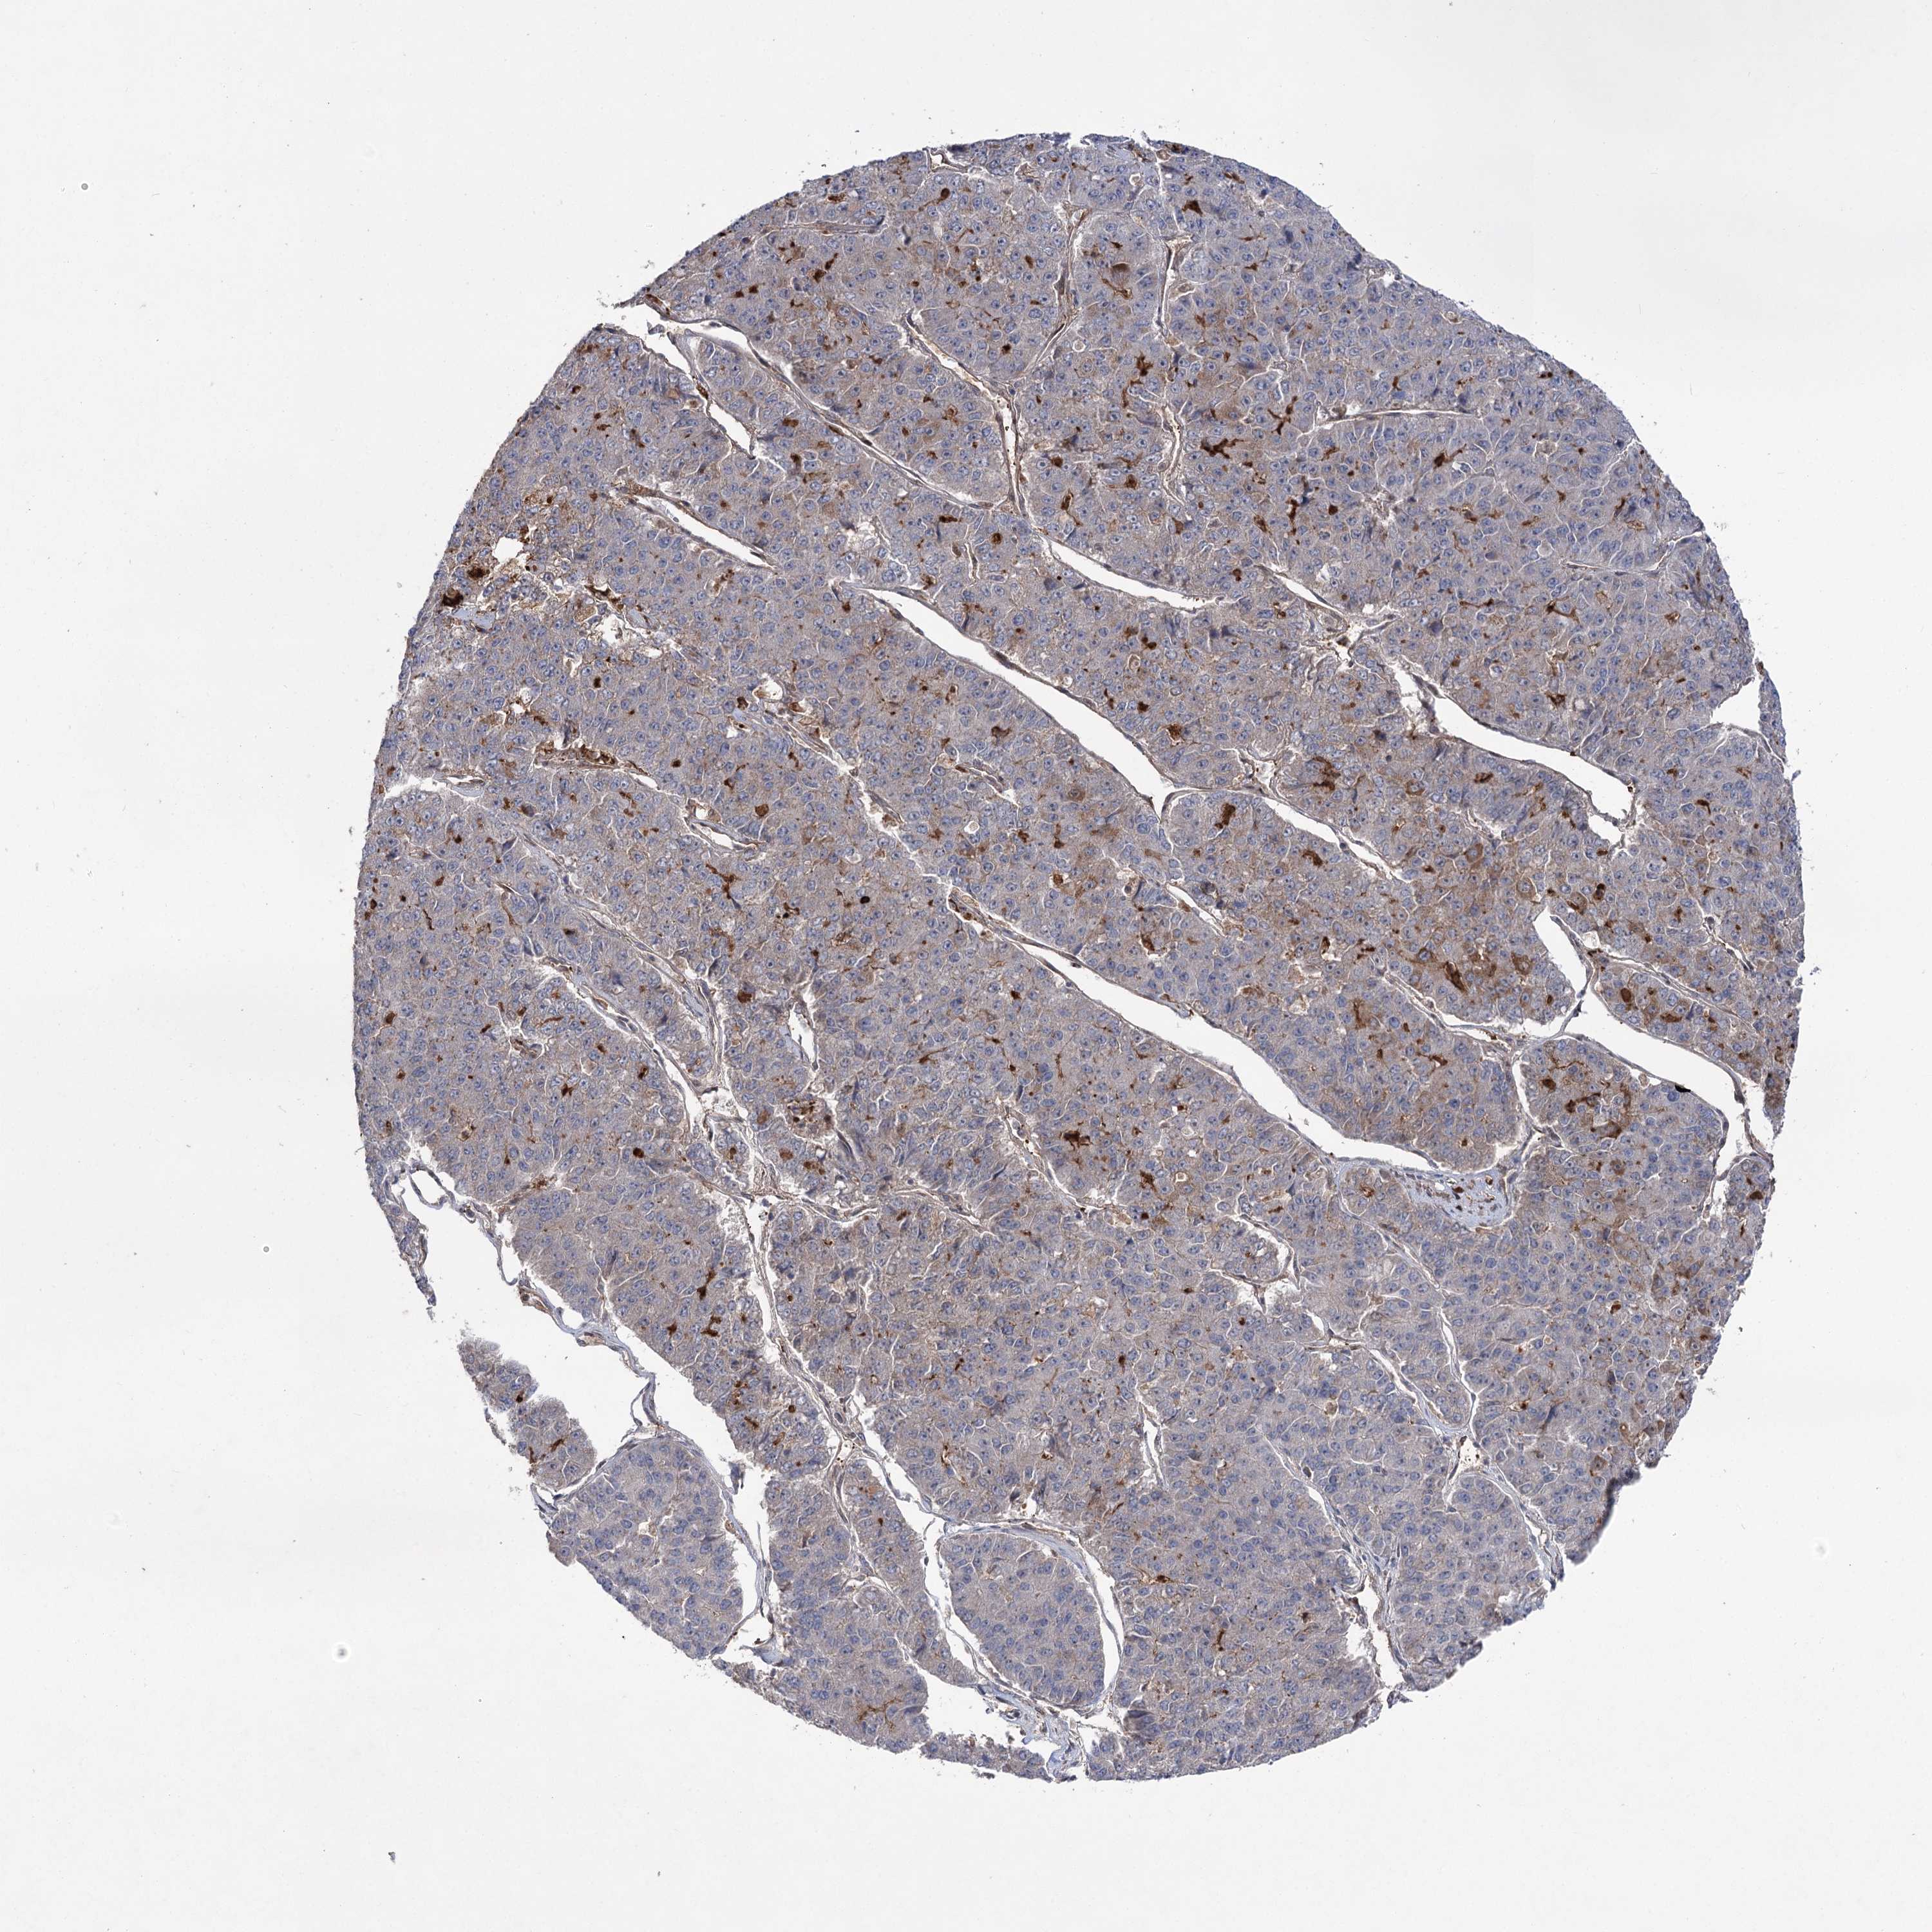

PANCREATIC CANCER - Protein expressioni

A mouse-over function shows sample information and annotation data. Click on an image to view it in a full screen mode. Samples can be filtered based on level of antibody staining by selecting one or several of the following categories: high, medium, low and not detected. The assay and annotation is described here.

Note that samples used for immunohistochemistry by the Human Protein Atlas do not correspond to samples in the TCGA dataset.

Antibody stainingi

Antibody staining in the annotated cell types in the current human tissue is reported as not detected, low, medium, or high, based on conventional immunohistochemistry profiling in selected tissues. This score is based on the combination of the staining intensity and fraction of stained cells.

Each image is clickable and will lead to virtual microscopy that enables deeper exploration of all samples and also displays staining intensity scores, fraction scores and subcellular localization as well as patient and tissue information for each sample.

Antibody HPA038504

Staining

High

Medium

Low

Not detected

Intensity

Strong

Moderate

Weak

Negative

Quantity

>75%

75%-25%

<25%

None

Location

Nuclear

Cytoplasmic/membranous

Cytoplasmic/membranous,nuclear

Adenocarcinoma, NOS